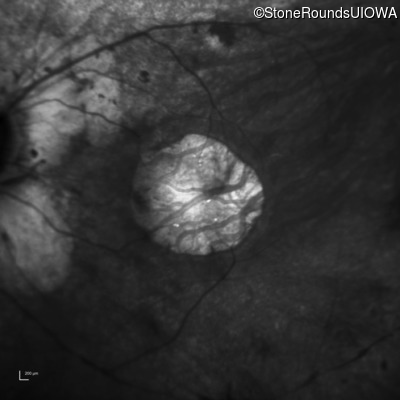

Age at visit: 15 years

OD OS

This 15 year old male had a macular abnormality noted two weeks ago when he was refracted for his first pair of glasses. Bone spicule-like pigmentation was first noticed a year later (age 16) during a routine follow-up eye exam.

Age at visit: 16 years